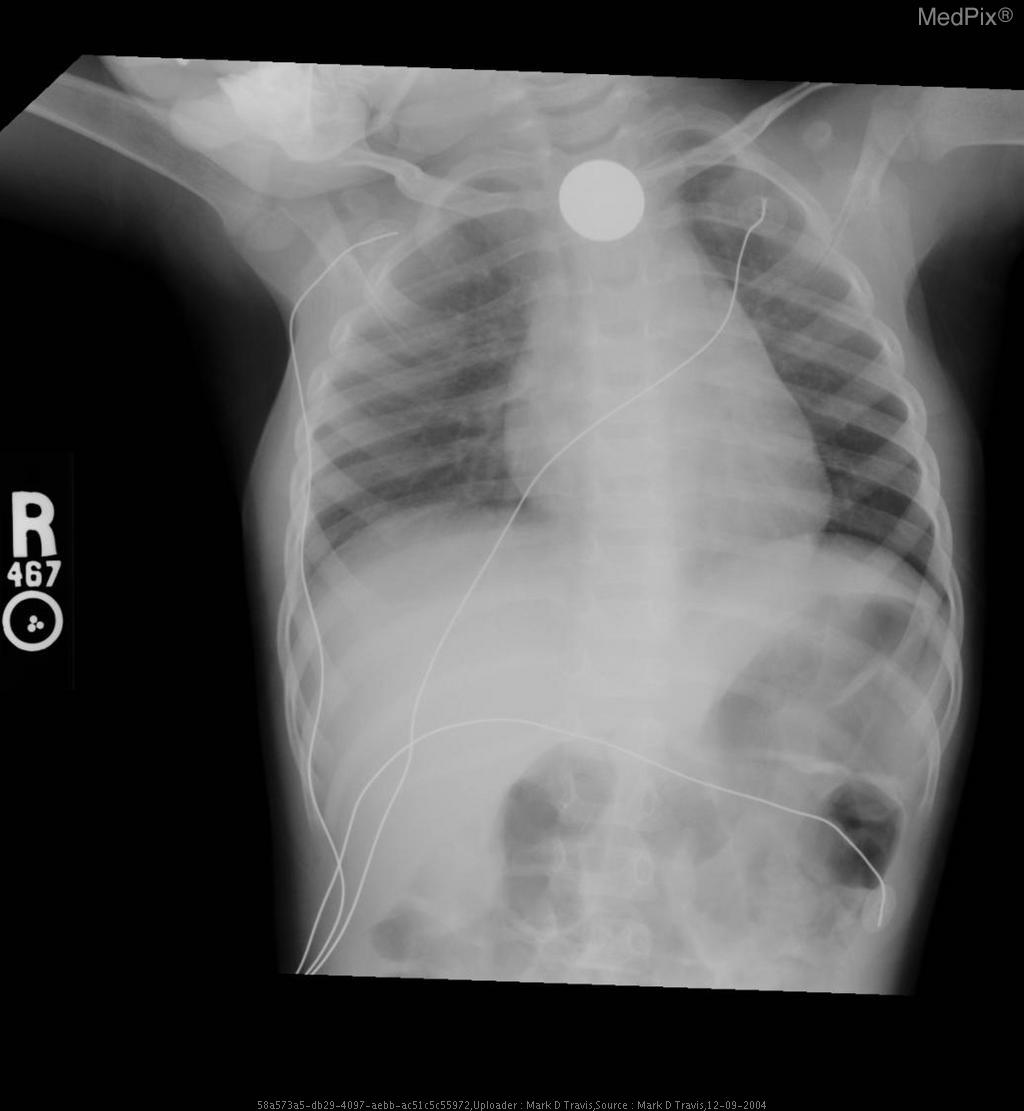

Esophageal foreign body - Coin ingestion

• Diagnosis: Esophageal foreign body

- Frontal chest and upper abdominal X-ray with standard orientation (image-left = patient-right).

- A well-circumscribed, round metallic density (coin) projects over the upper thoracic midline, posterior to the tracheal air column — typical of an object lodged in the esophagus rather than the trachea.

- No evidence of significant tracheal narrowing, suggesting airway is patent.

- Lung fields are clear bilaterally; no focal consolidation, effusion, or pneumothorax detected.

- Cardiothoracic ratio within normal range for age.

- Normal diaphragmatic contour and position; no subdiaphragmatic free air visualized.

- Enteric and monitoring tubes appear appropriately placed without complication.

2) Most likely diagnosis and why:

Esophageal foreign body (coin) lodged in the upper esophagus. The round metallic opacity centered over the thoracic midline and seen full-face on AP view indicates an esophageal (not tracheal) location—since tracheal foreign bodies appear more radiolucent and typically lie off-midline or show edge-on orientation. The absence of significant respiratory compromise supports esophageal lodging. Context consistency: Consistent — matches the provided context of “coin ingestion” in a pediatric patient. Confidence: 95%